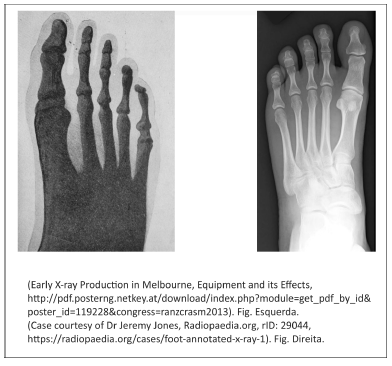

A figura da esquerda representa a primeira radiografia obtida na Austrália, em 1896, usando um tubo de raios catódicos de Crookes. A radiografia da direita é mais recente e evidencia a diferença de qualidade de imagem que se obtém hoje.

I. Os raios X não são idênticos aos raios catódicos, mas são produzidos pelos raios catódicos quando estes incidem na parede de vidro dos tubos de descarga de Crookes, utilizados na época da descoberta dos raios X.

II. O único fenômeno responsável pela produção dos raios X nos tubos de Crookes é a ionização.

III. A produção de imagens melhores (como a da direita) foi acompanhada por avanços tecnológicos que melhoraram a proteção radiológica de pacientes e trabalhadores ao lidar com tubos de raios X; entre eles, estão o cabeçote metálico do tubo e a tela intensificadora de imagens.